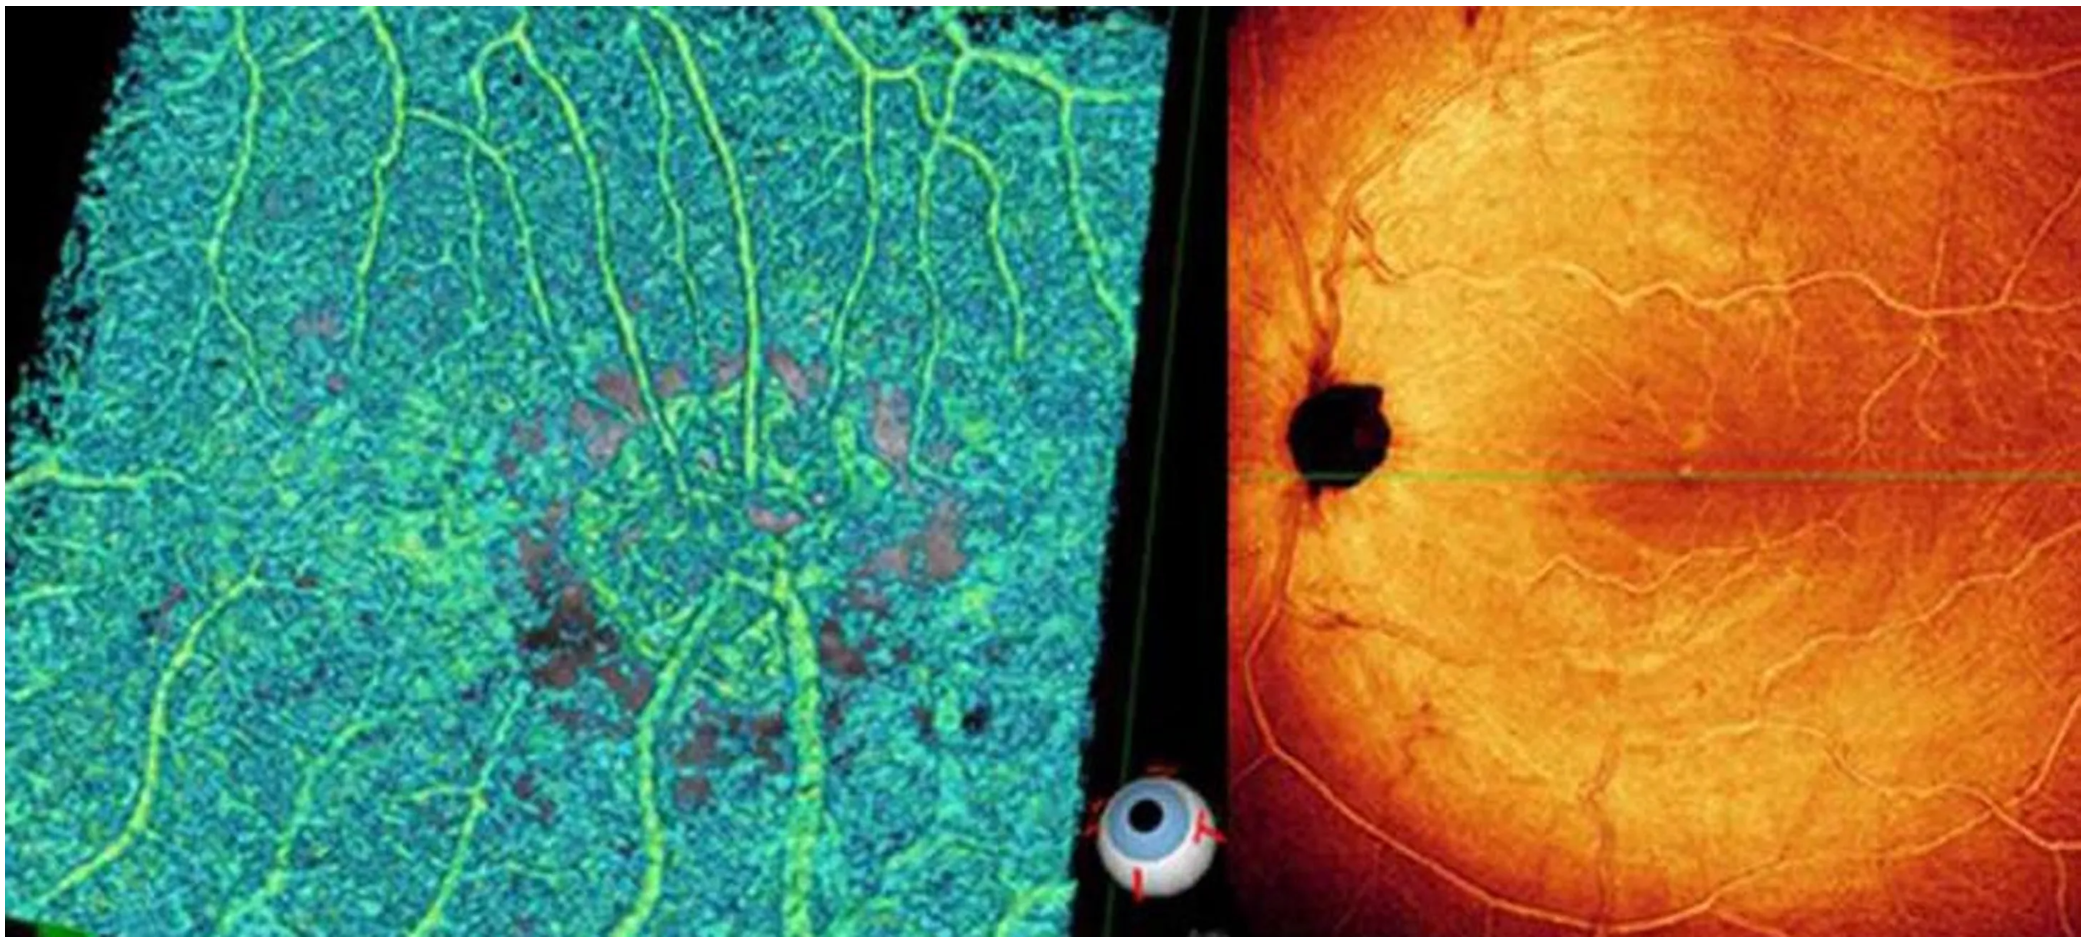

Оптический когерентный томограф Optovue Solix обладает повышенной скоростью сканирования — 120 000 А-сканов в секунду. SOLIX предоставляет множество инструментов для нового поколения борьбы с заболеваниями, которые повышают пропускную способность и обеспечивают превосходный уход за пациентами. В отличие от томографов более ранних поколений ОКТ SOLIX OPTOVUЕ может определять наличие конкрементов и новообразований сосудов сетчатки и хориоидеи, позволяет получать максимально точную послойную визуализацию структур глаза.

- Диапазон сканирования в режиме ангио-ОКТ — от 3х3 до 18х18 мм;

- Программа AngioAnaliticsTM для количественного анализа сосудов сетчатки;